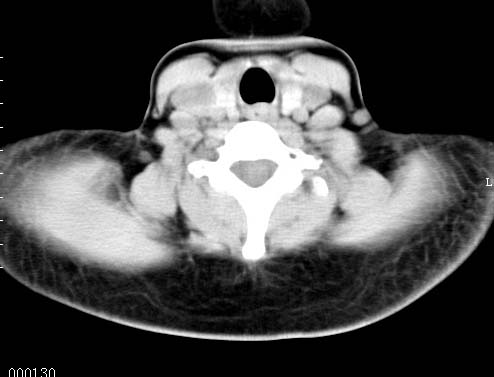

以下是引用sos.la在2008-6-24 5:29:00的发言:[br]可疑项部皮下脂肪肉瘤.穿刺活检.

以下是引用pujunzhi在2008-6-24 7:29:00的发言:[br]后颈部脂肪瘤

以下是引用随光逐影在2008-6-24 7:46:00的发言:[br]考虑项部皮下脂肪瘤或脂肪沉积。